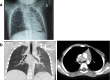

A 12-month-old boy, with no medical history, was admitted for dyspnoea with no cough or fever. Chest auscultation revealed an expiratory wheezing with decreased right-sided breath sounds. Chest imaging revealed subcarinal adenopathy and a nodule in the right principal bronchus (RB). Bronchoscopy showed a major obstruction of the RB by a granuloma, and a smaller granuloma in the left principal bronchus. The granulation tissue was removed by laser section. Histological examination revealed a necrotising granulomatous inflammation, culture showed a Mycobacterium avium complex (MAC). Tests to rule out tuberculosis and immunodeficiency were negative. The diagnosis of an MAC endobronchial granuloma was ascertained and a multidrug therapy associating clarithromycin, rifampin and ethambutol was started. The clinical outcome was good after 3 months of treatment and the bronchoscopy normalised after 1 year. Although rare, the frequency of MAC respiratory infections in immunocompetent children can increase. Reporting these cases should help to optimise diagnosis and treatment.